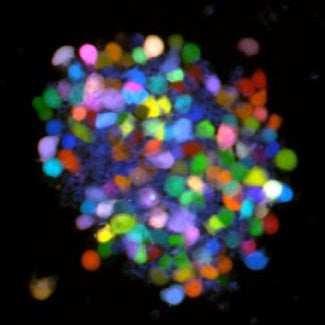

今回、同研究チームはRGBマーキング(注2)という手法を用いて七色に光るがん細胞を作製しました(図1)。この細胞をマウスの腹腔内に移植して、腹膜播種により形成された腫瘍を観察した結果、それぞれの腫瘍は複数の蛍光色を呈しており、複数のがん細胞集団から構成されることが分かりました。また、がん細胞は腹腔内でクラスターを形成し、集団で腹膜に接着して転移することが明らかになりました(図1)。さらに、がん細胞が発現する組織因子(注3)が腹腔内で血液凝固系を活性化してフィブリン(注4)の形成を誘導すること、このフィブリンが糊のように働きがん細胞同士をくっつけて、腹膜への接着を助けることを発見しました(図2)。実際にがん細胞の組織因子をノックアウトしてマウスに移植すると、フィブリンによるクラスター形成と腹膜播種が抑制されました(図3)。従って、がん細胞は組織因子により血液凝固系を活性化してフィブリン形成を誘導、腹腔内でクラスターを形成して集団で腹膜に接着することにより、多数の細胞集団から成るマルチクローナルな腫瘍を形成することが明らかになりました。

赤、緑、青の蛍光タンパク質を同時に胃がん細胞に導入し、個々の細胞を異なる蛍光色でラベルした。この細胞をマウスに移植し腹膜播種を誘導した。腹膜播種の腫瘍は1色ではなく複数の蛍光色を呈していた。また移植後の腹腔内にはがん細胞のクラスターが多数存在していた。従って、がん細胞は腹腔内でクラスターを形成し、集団で腹膜に接着してマルチクローナルな腫瘍を形成すると考えられた。